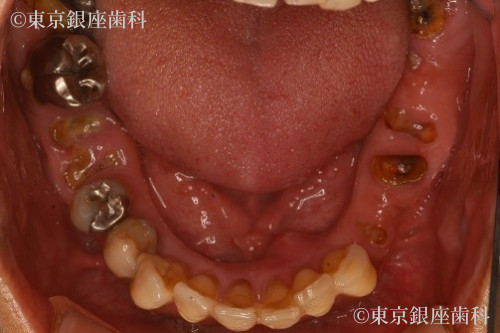

Before

すべての歯が今にも抜けそうなくらいに揺れており痛みを伴っていた為、まともな食事がとれずにいた。

5年後に来院した際には、歯周病が悪化し著しい歯の揺れ、歯の破折、骨の吸収が見られた。